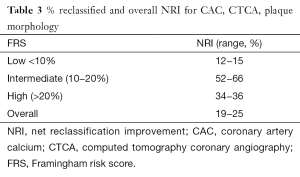

Prediction of outcomes using new tools involves more than association, discrimination, and calibration. Consequently current body of literature also emphasizes the importance of reclassification, such as net reclassification improvement (NRI) and integrated discrimination improvement (IDI). Analyzing the Multi-Ethnic Study of Atherosclerosis (MESA) cohort, Yeboah demonstrated that CAC provided superior discrimination and risk reclassification over FRS, ankle-brachial index, high-sensitivity CRP and family history, though all were independent predictors of cardiovascular disease in intermediate risk individuals. Hecht and Narula summarized three studies (MESA, Heinz Nixdof, and Rotterdam) (12-14) and found an NRI of 19−25% (15) (Table 3). Hecht has also surmised from multiple studies that a CAC of 0 is associated with a 10-year event of 1.1−1.7%. There is an incremental risk with increasing CAC score of: 1−100 (2.3−5.9%), 101−400 (12.8−16.4%), >400 (22.5−28.6%) and >1,000 (37%) (16). Valenti has shown that in low to intermediate risk individuals, a CAC scores of 0 confers a 15-year warranty of <1% annual mortality (17). In summary, the CAC primarily serves as a risk stratification tool for primary prevention cohorts to provide incremental prognostic value and once evidence catches up- influence management decisions.